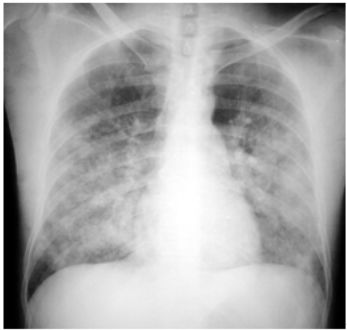

3. 病人18歲女計程車無線呼叫員, 到院主訴有五天的間 歇性燒熱及寒顫(chillness), 並合併頭痛、雙眼後疼痛及全身肌疼, 經初步診斷腦膜炎, 病人拒絕腰椎穿刺檢查, 乃試用抗生素後回家療養。 唯症狀仍舊, 尚有噁心、嘔吐, 並先後在左大拇指及右小趾出現疼痛紅斑(如圖A及B所示)。既往病史有二尖瓣膜脫垂及閉鎖不全。理學所見身高:162cm;體重:45Kg;BP:105/67mmgHg;T/P/R: 39.8C/155/18。未見Meningeal signs. 頸部末見異常, 心尖在left 5th ICS, mid-clavicular line, 有Grade III/VI Pansystolic murmur. S1及S2正常。胸、腹都無不正常。實驗室檢查: WBC:4.39x k/uL,有left shifting;RBC:5.12 x M/uL;Hb:11.0 g/dL;Platelets:130 x K/uL;其血液細菌培養結果如與胸部X光詳見附圖C、D。心電圖如附。本病人經過下列臨床處置